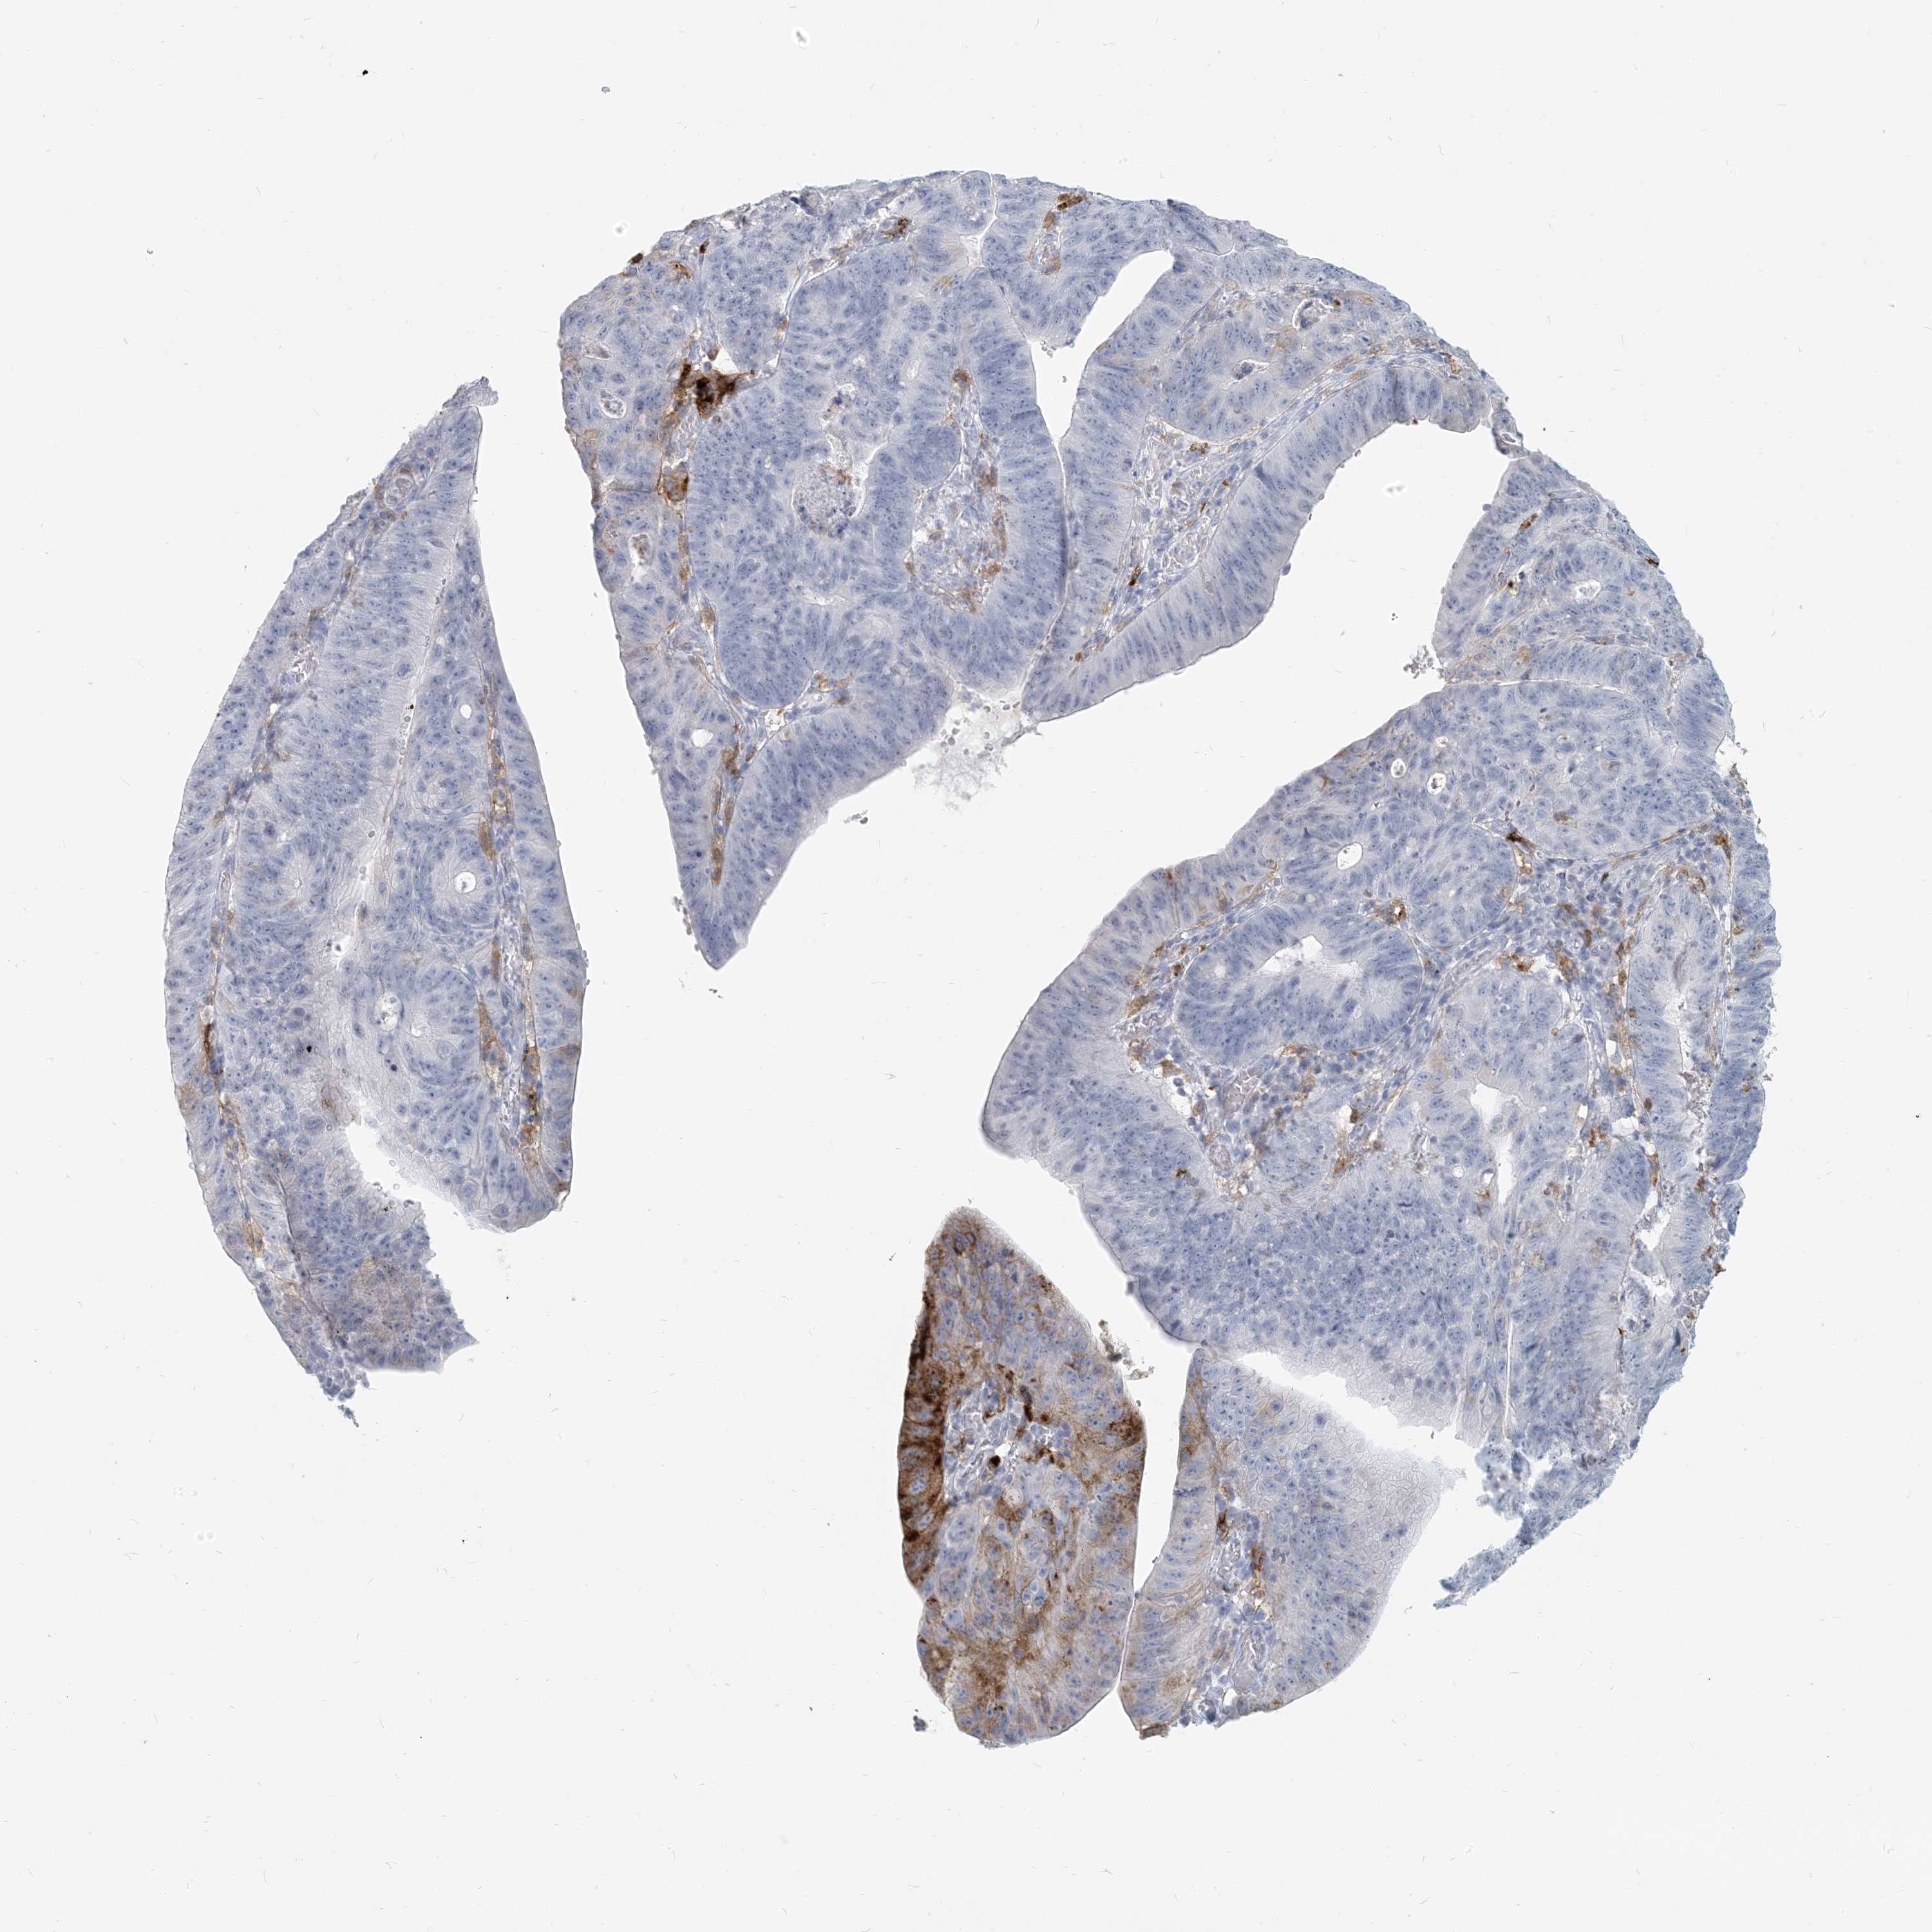

STOMACH CANCER - Protein expressioni

A mouse-over function shows sample information and annotation data. Click on an image to view it in a full screen mode. Samples can be filtered based on level of antibody staining by selecting one or several of the following categories: high, medium, low and not detected. The assay and annotation is described here.

Note that samples used for immunohistochemistry by the Human Protein Atlas do not correspond to samples in the TCGA dataset.

Antibody stainingi

Antibody staining in the annotated cell types in the current human tissue is reported as not detected, low, medium, or high, based on conventional immunohistochemistry profiling in selected tissues. This score is based on the combination of the staining intensity and fraction of stained cells.

Each image is clickable and will lead to virtual microscopy that enables deeper exploration of all samples and also displays staining intensity scores, fraction scores and subcellular localization as well as patient and tissue information for each sample.

Antibody HPA043151

Antibody CAB015400

Antibody CAB034021

Staining

High

Medium

Low

Not detected

Intensity

Strong

Moderate

Weak

Negative

Quantity

>75%

75%-25%

<25%

None

Location

Nuclear

Cytoplasmic/membranous

Cytoplasmic/membranous,nuclear

Adenocarcinoma, NOS